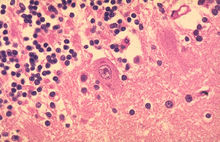

Základní metodou diagnostiky vztekliny u zvířat i lidí je nepřímá imunofluorescence, která se dělá z otisků řezů mozku (Amonův roh). Imunofluorescencí se prokazují virové antigeny přímo ve tkáni nakaženého jedince, je vysoce senzitivní a specifická a také relativně rychlá, přesná a levná. Jedná se ovšem o postmortální způsob diagnostiky a nedá se použít při diagnostice vztekliny u lidí (jedině jako metoda potvrzení po úmrtí pacienta). V minulosti se dělaly také histologické řezy, u nemocných se často vyskytovaly typické intracytoplasmatické inkluze (tvořené virovými proteiny) zvané Babes-Negriho tělíska. Nejčastěji se tvoří v Purkyňových a pyramidálních buňkách Amonova rohu. Přestože jsou patognomickým znakem pro vzteklinu, od použití histologie se v diagnostice vztekliny upustilo, jejich nepřítomnost totiž vzteklinu ani zdaleka nevylučuje. Biologický pokus, při kterém se suspenze z vyšetřované tkáně inokuluje 3-5 denním myškám a následně se provádí nepřímá imunoflourescence z jejich mozkové tkáně, se provádí vždy v případě pokousání člověka. Intravitální metody jsou méně přesné a specifické a používají se jenom u lidí (zvířata, u kterých je vážné podezření na vzteklinu jsou utracena a vyšetřena imunofluorescencí). Používají se otiskové preparáty z rohovky, které se vyšetřují pomocí IF, izolace viru ze slin nemocného a sérologické průkazy protilátek v krvi nebo mozkomíšním moku. PCR slouží k průkazu virové RNA. Negativní výsledky však vzteklinu nevylučují.